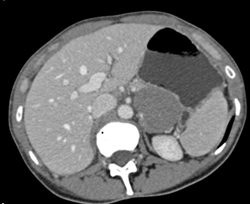

GIST Tumor